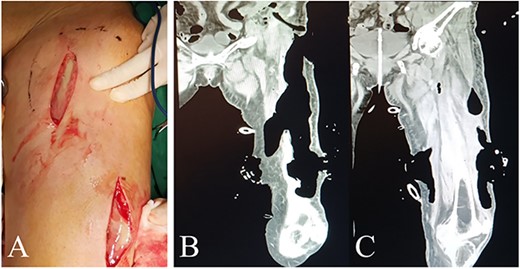

The first surgery was performed several hours after admission, aiming to debride necrotic tissue and pus for infection control, and to take tumor specimens for pathological examination. Multiple longitudinal incisions were made for drainage to avoid the perforators being damaged, which may lead to extensive skin necrosis in the blood supply area. During the surgery, a large amount of pus and gas overflowed from under the skin of the whole thigh and each intermuscular space with distinct stench of dung (Fig. 2A). Extensive necrosis was found in the subcutaneous fat fascia and the intermuscular fascia. Pus samples were taken for drug sensitivity test and bacterial culture. Blunt dissection was performed carefully and necrotic tissue under direct vision was excised, followed by repeated irrigation with huge amount of hydrogen peroxide and normal saline.

Intraoperative view and postoperative CT of left thigh in the first operation. (A) Intraoperative anterior view of left thigh. (B) and (C) Coronal planes from CT 7 days after the first operation display areas dressed with VSD (PU) material.